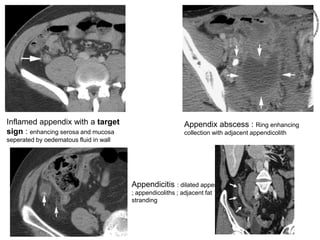

Acute appendicitis

Transverse U/S : Inflammed

appendix (between calipers) ;

adjacent inflamed fat (arrow) ;

terminal ileum with air (curved arrow)

Longitudinal U/S : inflammed

appendix with proximal

appendicolith

Inflamed appendix with a target

sign : enhancing serosa and mucosa

seperated by oedematous fluid in wall

Appendix abscess : Ring enhancing

collection with adjacent appendicolith

Appendicitis : dilated appendix

; appendicoliths ; adjacent fat

stranding

Transverse U/S :Inflammed appendix (between calipers) ; adjacent inflamed fat (arrow) ; terminal ileum with air (curved arrow) Longitudinal U/S : inflammed appendix with proximal appendicolith

Inflamed appendix witha target sign : enhancing serosa and mucosa seperated by oedematous fluid in wall Appendix abscess : Ring enhancing collection with adjacent appendicolith Appendicitis : dilated appendix ; appendicoliths ; adjacent fat stranding